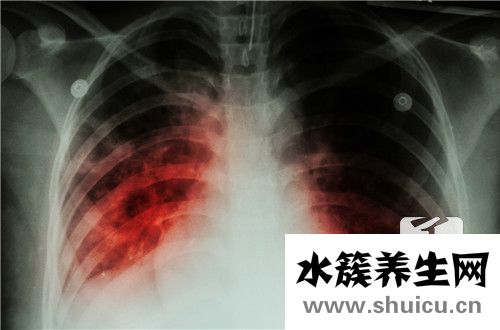

?在生活中,我非常擔心各種癌癥問題,因為癌癥可能是無法治愈的疾病,即使治愈,它也可能擴散或復發(fā)。 實際上,手術后會有一些患者。 炎癥需要數年才能被完全殺死。

1、肺癌術后的后續(xù)治療 II期以上的肺癌患者一般在術后3-4周接受輔助化療,化療通常三周一次,4-6次。Ia期患者在接受肺癌手術后不要輔助化療,一定要注意保持樂觀開朗的心情,長期定期隨訪,術后兩年內每三個月復查一次,之后每半年一次,至第五年后可延長至每年復查一次。堅信肺癌是可以治愈,正確面對癌癥,積極生活。

2、肺癌手術后的飲食 肺癌手術的注意事項中飲食的原則宜清淡、細軟、容易消化吸收為主,在食物選擇與進補時,不要急于求成,可從流質飲食開始,無明顯不適反應時,再過渡到半流食、普食,選擇飲食時,還應注意各種營養(yǎng)平衡,以利于術后機體的康復。在恢復期間,維持正常飲食,除了辛辣刺激性食物、油炸食品、煙酒外無忌口,多吃新鮮蔬菜和水果,如綠、黃、紅蔬菜以及黑木耳、杏仁露、荸薺、蘆筍、檸檬、紅棗、甲魚、黃魚、甜杏仁、核桃,大棗、香菇等。另外,根據癥狀表現的不同,有針對性地選用有止咳、退熱、止血、順氣、寬胸、止痛作用的食品,以減輕痛苦。

3、肺癌手術后的生活護理 肺癌手術后的生活護理也可以從心理和生理兩方面講。在心態(tài)方面,早期肺癌患者需明白術后有可能出現復發(fā)也有可能完全治愈,要對自己的病情和治療期間的副反應有正確的認識,務必保持樂觀開朗的情緒,堅信自己一定能夠戰(zhàn)勝疾病。只有調整心態(tài),樹立信心,積極配合治療,才能調動身體內部的抗病機制,消極悲觀,終日憂愁是否會復發(fā)對康復是非常不利的。

生理方面,除了飲食調理外,患者要重視呼吸道的保養(yǎng),注意氣候冷暖變化,盡量避免感冒,如果發(fā)生上呼吸道感染,應及時就醫(yī)用藥,徹底治療,以免發(fā)生肺炎。

不要在空氣污濁的場所停留,避免吸入二手煙。若出現一些刺激性咳嗽無需緊張,有痰時一定要及時咳出,如果痰較為粘稠,可服用一些祛痰藥物如沐舒坦等;如果咳嗽較嚴重影響休息的,可選擇服用輕度鎮(zhèn)咳藥物如復方甘草合劑、開瑞坦等;如果感覺手術傷口有針刺樣疼痛和麻木感,與手術時切斷了胸壁的神經有關,此時患者家屬應安慰患者需耐心等待,幫其分撒注意力。數月后,這種不適感才會慢慢消退。

肺癌患者術后注意:傷口、坐臥姿治療后肺癌患者術后注意應盡量少出入公共場所,以免出現傷口感染;患者應避免提重物,以免出現撕裂傷口現象;應時常注意自身傷口愈合情況,如出現紅、腫、熱、痛或發(fā)燒的情況應及時返回醫(yī)院檢查;注意坐臥姿勢,應以半坐臥為佳,因為橫膈膜往下會使肺部擴張,影響到呼吸。